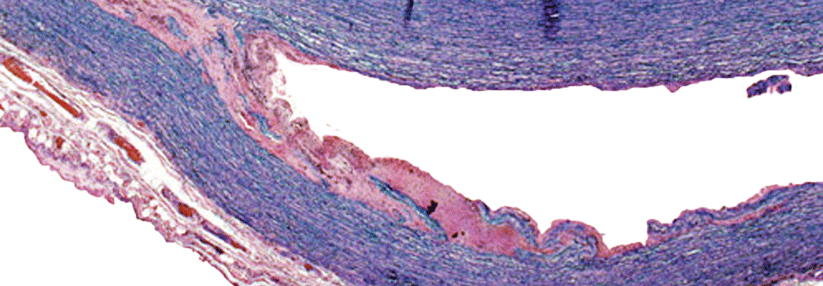

Wird eine ILD diagnsotiziert, finden sich bei dem RA-Patienten in der Regel eine hohe Rheumaaktivität und ein hoher Titer von Antikörpern gegen das zyklische citrullinierte Peptid (CCP). In der hochaufgelösten Computertomographie (HR-CT) sprechen bilaterale subpleurale und basale Retikulationen und Honigwaben mit und ohne Traktionsbronchiektasien für ein UIP (Usual Interstitial…